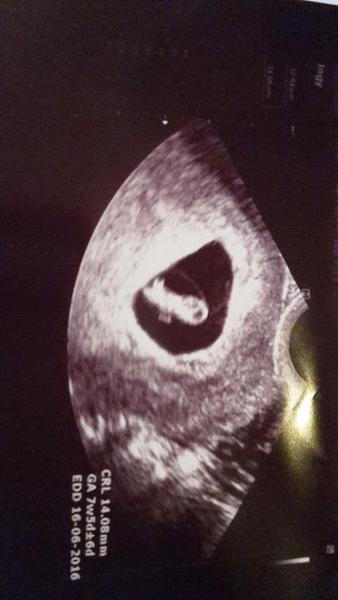

@romelia to je, ale krásnej mimozemšťánek 🙂 moc velká gratulace a hlavně zdravíčko mamčo 🙂

Moc blahopřeji, fotečka je krásná....

Téééda, fakt mimozemšťan 😀 gratuluji.